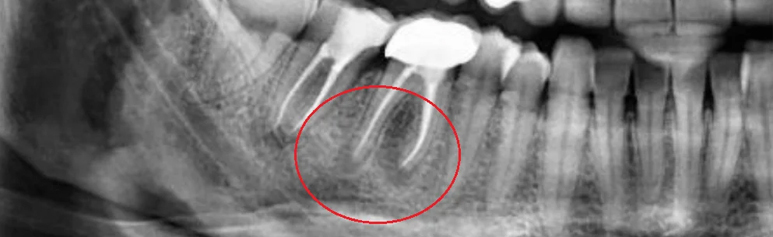

Sometimes, Dental Granuloma remains symptomless and is discovered only during an X-ray or routine dental visit.

Diagnosis of a Dental Granuloma requires a careful clinical and radiographic examination by an experienced dentist.

Here’s how it is typically identified:

At a trusted dental hospital in Chennai advanced imaging and precision diagnostics are used to detect even small granulomas early ensuring the right treatment approach.